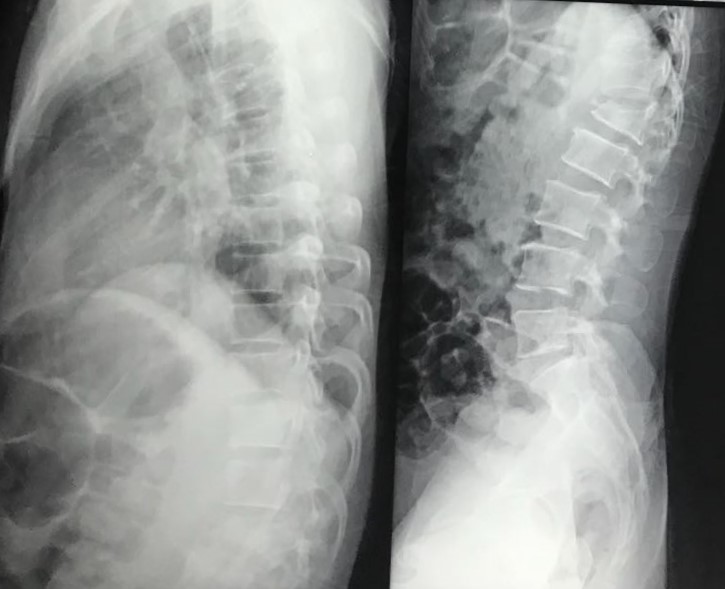

13 yrs female with cong kyphoscoliosis and d10 posterolateral wedge hemivetebra.

kyphosis 104 degree and scoliosis 43degrees.

Did vcr d10 with correction of deformity, fixation and fusion. Post op spine balnced in both sagittal and coronal planes.

Patient neurology intact. Mobilised.